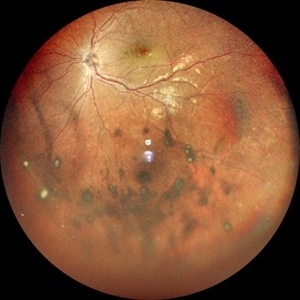

---thumb.jpg/image-square;max$300,300.ImageHandler) Intermediate Uveitis and CME

Intermediate Uveitis and CME

Feb 26 2013 by Henry J. Kaplan, MD

Cystoid macular edema in intermediate uveitis.

Condition/keywords: cystoid macular edema (CME), intermediate uveitis